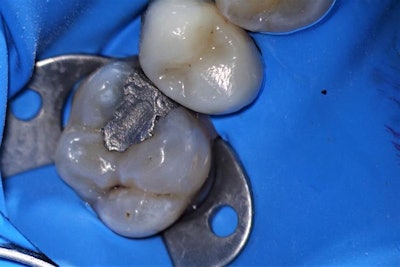

A 30-year-old man presented to the dental practice with a chief complaint of a sensitive tooth on the upper left posterior. Upon examination, the patient's discomfort was found to be due to decay and a leaking old amalgam on tooth #14. A thermal test produced normal results, and a diagnosis of reversible pulpitis was determined.

The clinical objective was to remove the old amalgam and decay and restore the tooth with a composite material, a rather common restorative situation. In this case, Clearfil Majesty ES-2 Universal (Kuraray Noritake Dental) single-shade composite was chosen due to the material's simplicity, ease of use, and ability to blend in with no need for blocker or opaquer in most clinical situations.

The procedure began by isolating the affected tooth from oral fluids using a rubber dam, followed by the mechanical removal of the amalgam and decay as completely, yet conservatively, as possible to maximize tooth structure preservation. Next, removal of the biofilm layer was achieved using a prophy jet handpiece.